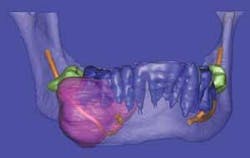

Stereolithography is also known in the industrial world as rapid prototyping. Dental CBCT scans processed using Sim Plant® software can be digitally transformed for creating stereolithographic models. Rapid prototyping allows the fabrication of physical replicas of 3-D computer-generated models in a layered approach. After the 3-D rendition is generated, software slices the file from top to bottom and then the slice data is sent to a machine that fabricates the part slice by slice. In dentistry, the fabrication of biomodels gives the oral surgeon a full-volume plastic template to plan surgical procedures, fabricate custom-engineered joint- and bone-replacement prostheses, and model facial-plastic reconstructive procedures (see Figures 8a and 8b).